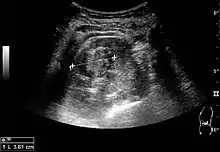

Cortical solid mass, which later was shown to be renal cell carcinoma. Measurement of the solid mass on the US image is illustrated by ‘+’ and a dashed line.[3]

On renal ultrasonography, a solid renal mass appears in the US exam with internal echoes, without the well-defined, smooth walls seen in cysts, often with Doppler signal, and is frequently malignant or has a high malignant potential. The most common malignant renal parenchymal tumor is renal cell carcinoma (RCC), which accounts for 86% of the malignancies in the kidney. RCCs are typically isoechoic and peripherally located in the parenchyma, but can be both hypo- and hyper-echoic and are found centrally in medulla or sinus. The lesions can be multifocal and have cystic elements due to necrosis, calcifications and be multifocal (Figure 8 and Figure 9). RCC is associated with von Hippel–Lindau disease, and with tuberous sclerosis, and US has been recommended as a tool for assessment and follow-up of renal masses in these patients.[3]